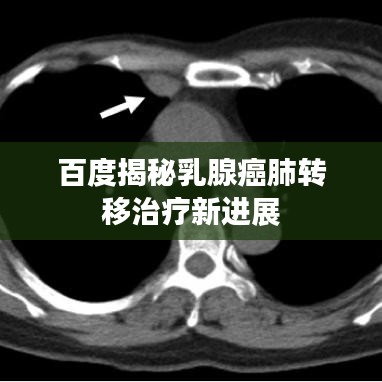

乳腺癌是女性常见的恶性肿瘤之一,而肺转移是乳腺癌患者可能出现的一种严重并发症,当乳腺癌细胞扩散到肺部时,治疗变得更加复杂,了解乳腺癌肺转移的相关知识,对于患者和医生来说都至关重要。

乳腺癌肺转移的症状包括咳嗽、呼吸困难、胸痛等,当患者出现这些症状时,应及时就医,进行详细的检查和治疗。